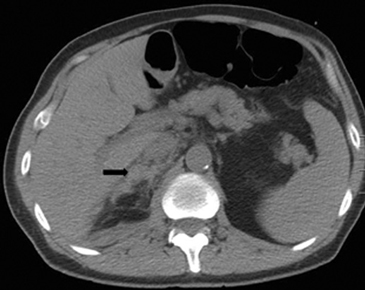

Tanto las lesiones benignas como malignas pueden presentar una atenuación heterogénea, especialmente en fases contrastadas, pero la presencia de grandes focos necróticos son mas bien orientadores de malignidad (Figura 8 a y b).

En TC sin contraste por lo general se observa una masa heterogénea, especialmente en caso de lesiones de mayor tamaño por la presencia de necrosis. Entre un 19 a 33% de los casos se identifican calcificaciones. Luego de la administración de contraste su refuerzo es heterogéneo y su patrón de lavado es consistente con una enfermedad maligna (Figura 22).